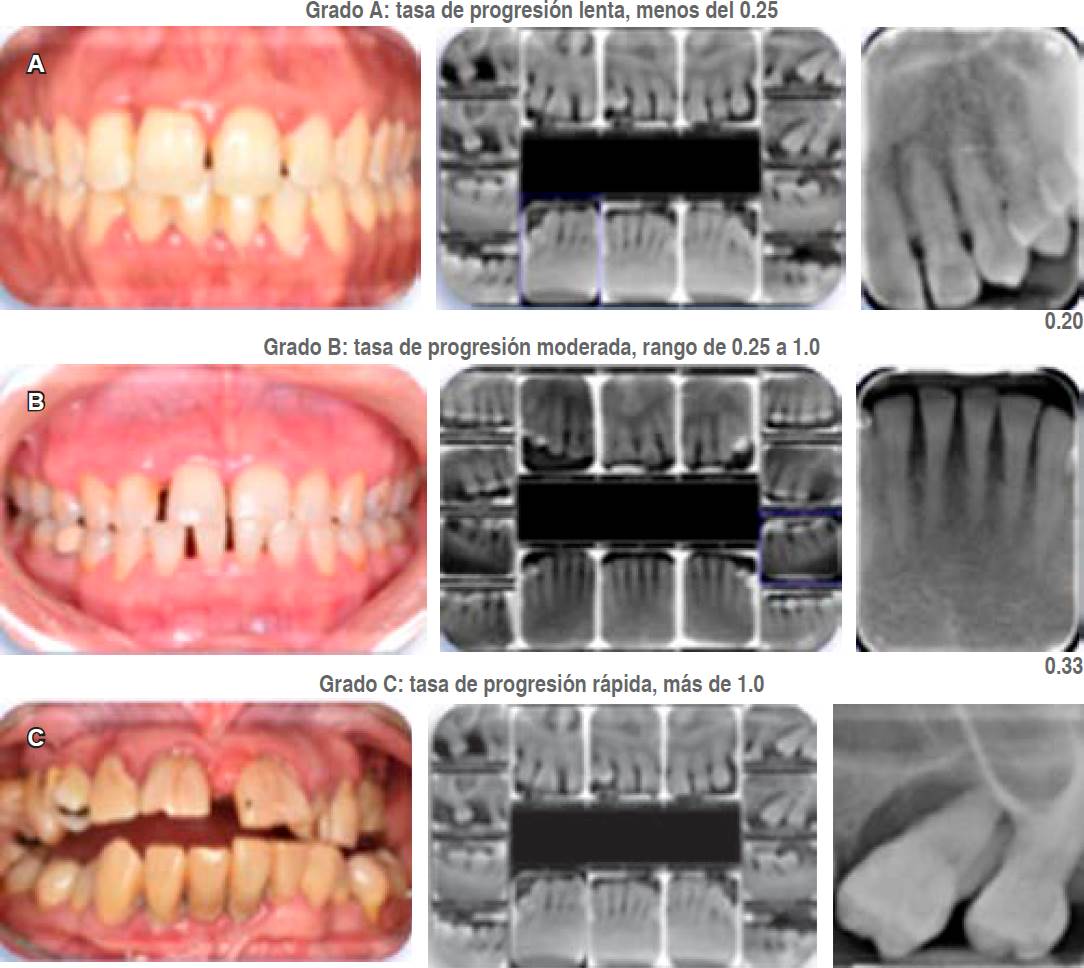

c. Grados. El grado es un indicador de la velocidad o tasa de progresión de la periodontitis. Se categoriza en un grado de progresión lenta (A), moderada (B) y rápida (C). Para asignar el grado, el criterio principal puede ser obtenido a través de:

Evidencia indirecta de progresión: al carecer de datos previos de la pérdida ósea radiográfica o de inserción clínica, se puede determinar el grado por el porcentaje de pérdida ósea presente en el diente más afectado dividida entre la edad del paciente. El grado A corresponde cuando el resultado es menor de 0.25, el grado B abarca de 0.25 a 1.0, y el grado C corresponde a más de 1.0 (Figura 6).19

En la Tabla 5 se muestran los parámetros a tomar en consideración para asignar los grados y la Figura 7 ejemplifica casos clínicos para cada grado.

Figura 7 Casos clínicos. A) Grado A con una velocidad o tasa progresión lenta. B) Grado B con una velocidad o tasa progresión moderada. C) Grado C con una velocidad o tasa progresión rápida.

Los clínicos deben asumir primero el grado B de la periodontitis y buscar evidencia específica para el cambio hacia el grado A o al C si está disponible. Una vez que se ha establecido el grado, puede ser modificado con base en la presencia de factores de riesgo.19